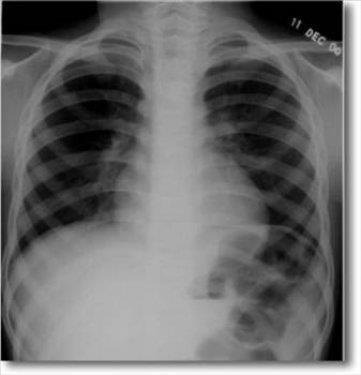

3. Kazakistan'da 7 yaşındaki bir erkek çocuğun karnında ikizi bulundu.

Kazakistan'da 7 yaşındaki bir erkek çocuğun karnında ikizi bulundu.

4. Simkent şehrinde yaşayan çocuğun karnındaki şişliği fark eden okul doktorunun hastaneye başvurması sonucunda hemen ameliyata alınan çocuğun karnından saçları ve tırnakları uzamış bir cenin çıkarıldı.

Simkent şehrinde yaşayan çocuğun karnındaki şişliği fark eden okul doktorunun hastaneye başvurması sonucunda hemen ameliyata alınan çocuğun karnından saçları ve tırnakları uzamış bir cenin çıkarıldı.